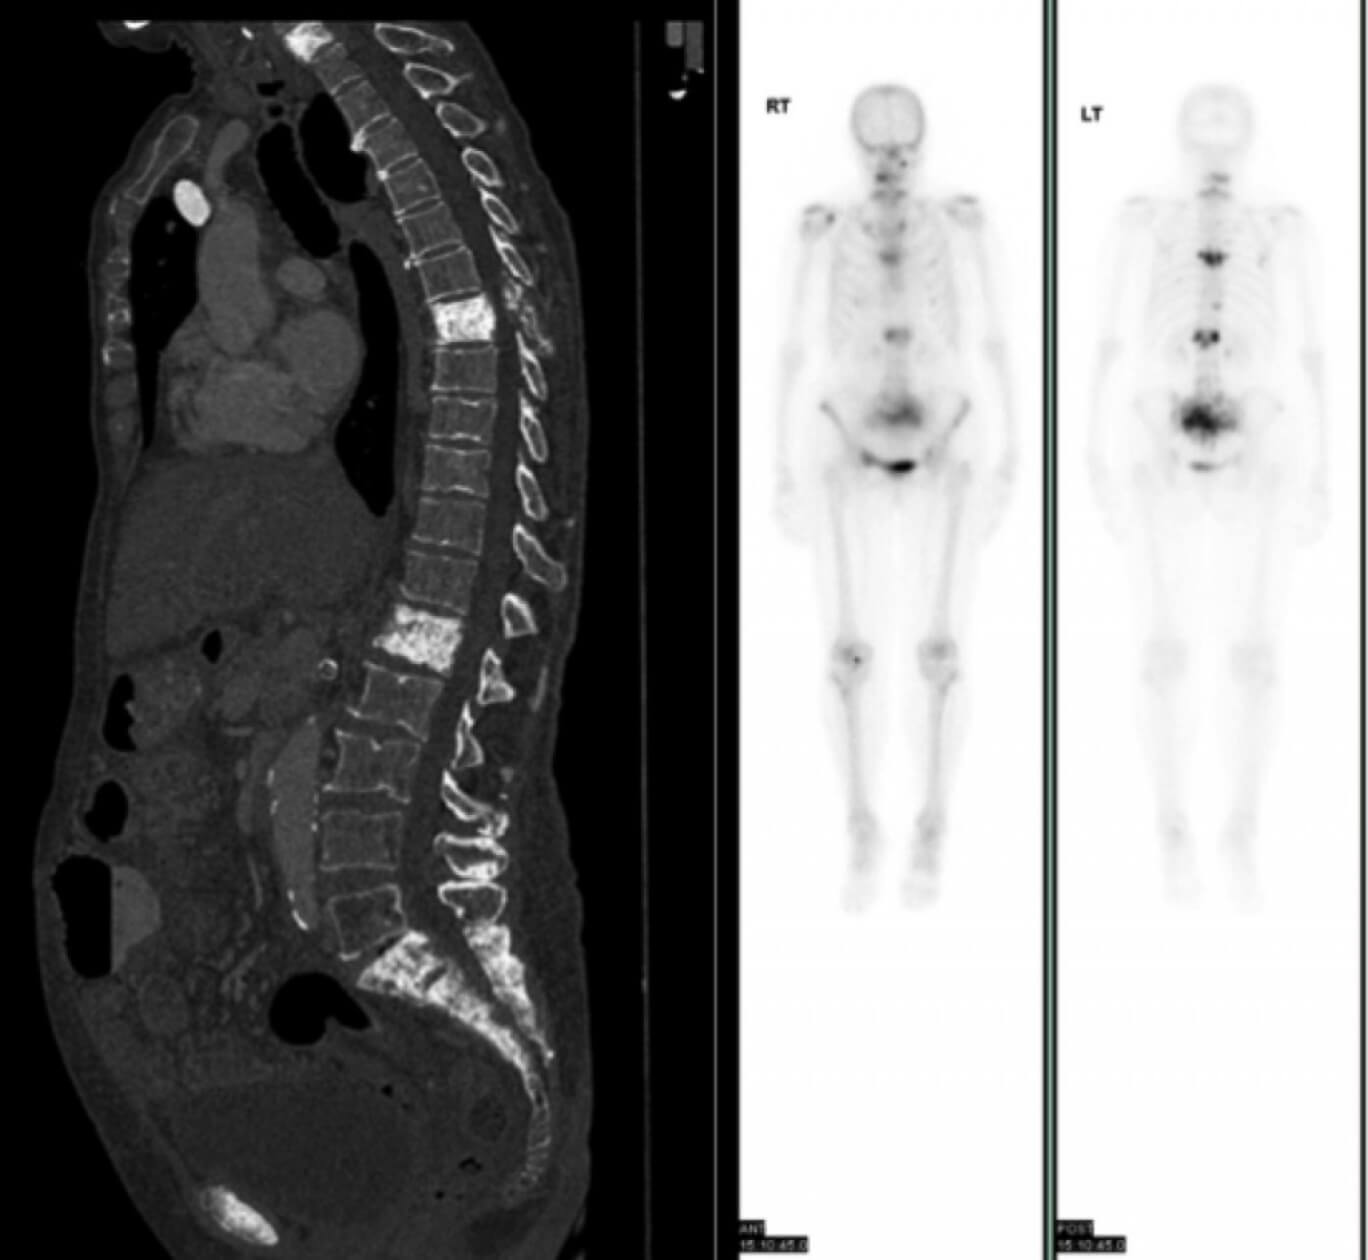

По данным остеосцинтиграфии и компьютерной томографии также выявлено поражение позвоночника:

Рис. 3 — отмечается литическое поражение тел позвонков поясничного отдела, поражение остистого отростка L3, патологический перелом тела позвонка L1.